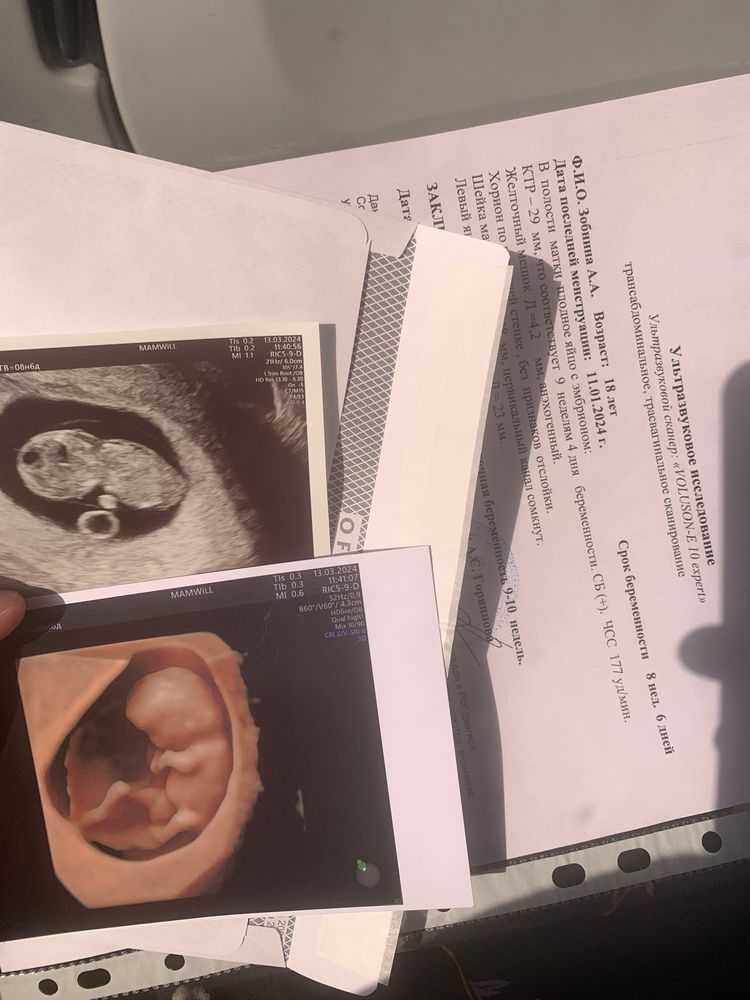

Узи 9 недель

Не паникуйте. Не понимаю врача, которая Вас напугала на таком сроке. ТВП измеряется ТОЛЬКО сроке 12 недель, т.е. на первом скрининга. Также ТВП смотрят вместе с КТР, если уже ТВП больше 3 будет на скрининге, тогда уже стоит дальше обследоваться и искать причину. Сейчас Вам просто бессмысленно измерили ТВП и напугали, успокойтесь и ждите скрининга. Хорошей беременности🌸

Определение срока на 12 неделе Как думаете кто, девочка или мальчик???